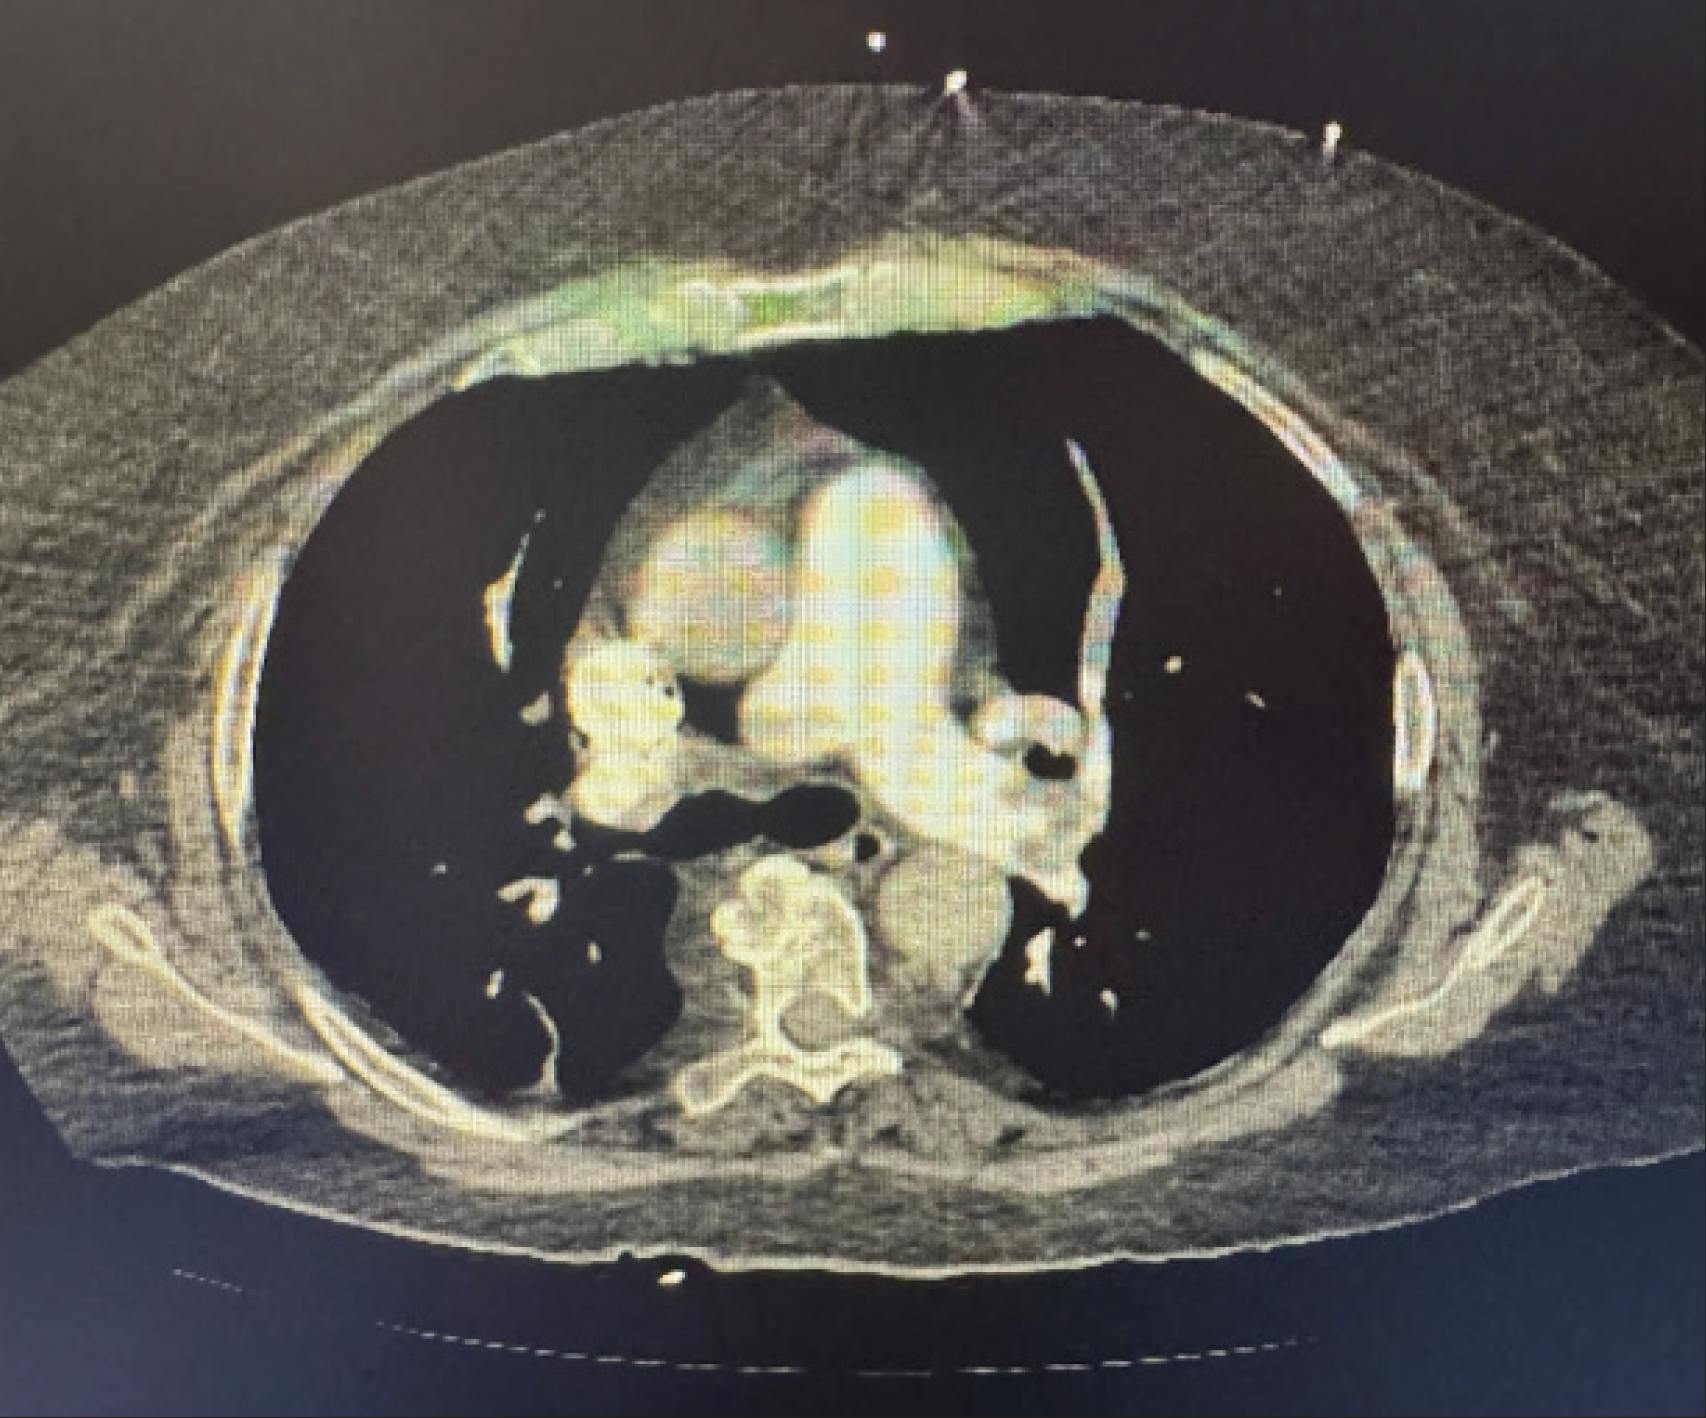

A female patient in her early 70s with a medical history of left posterior cerebral artery (PCA) stroke with residual right-sided weakness (20 years prior), hypertension, hyperlipidemia, hypothyroidism, and mild dementia was admitted to the hospital by a family member after collapsing. CT pulmonary angiography (CTPA) demonstrated RV strain and a saddle PE (Figure 1). Initial brain natriuretic peptide (BNP) and high-sensitivity troponin levels were negative; however, repeat testing showed a high-sensitivity troponin level of 228 ng/L and BNP of 1,549 pg/mL. After discussion with the patient and her family, MT was pursued, as no other reversible cause for syncope was identified.

Figure 1. Initial CTPA showing evidence of RV strain and saddle PE.